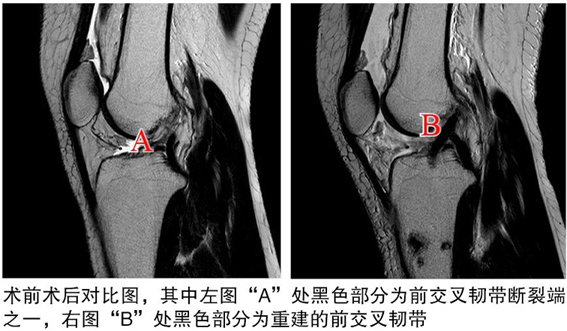

術后

關節(jié)鏡下見重建的前交叉韌帶